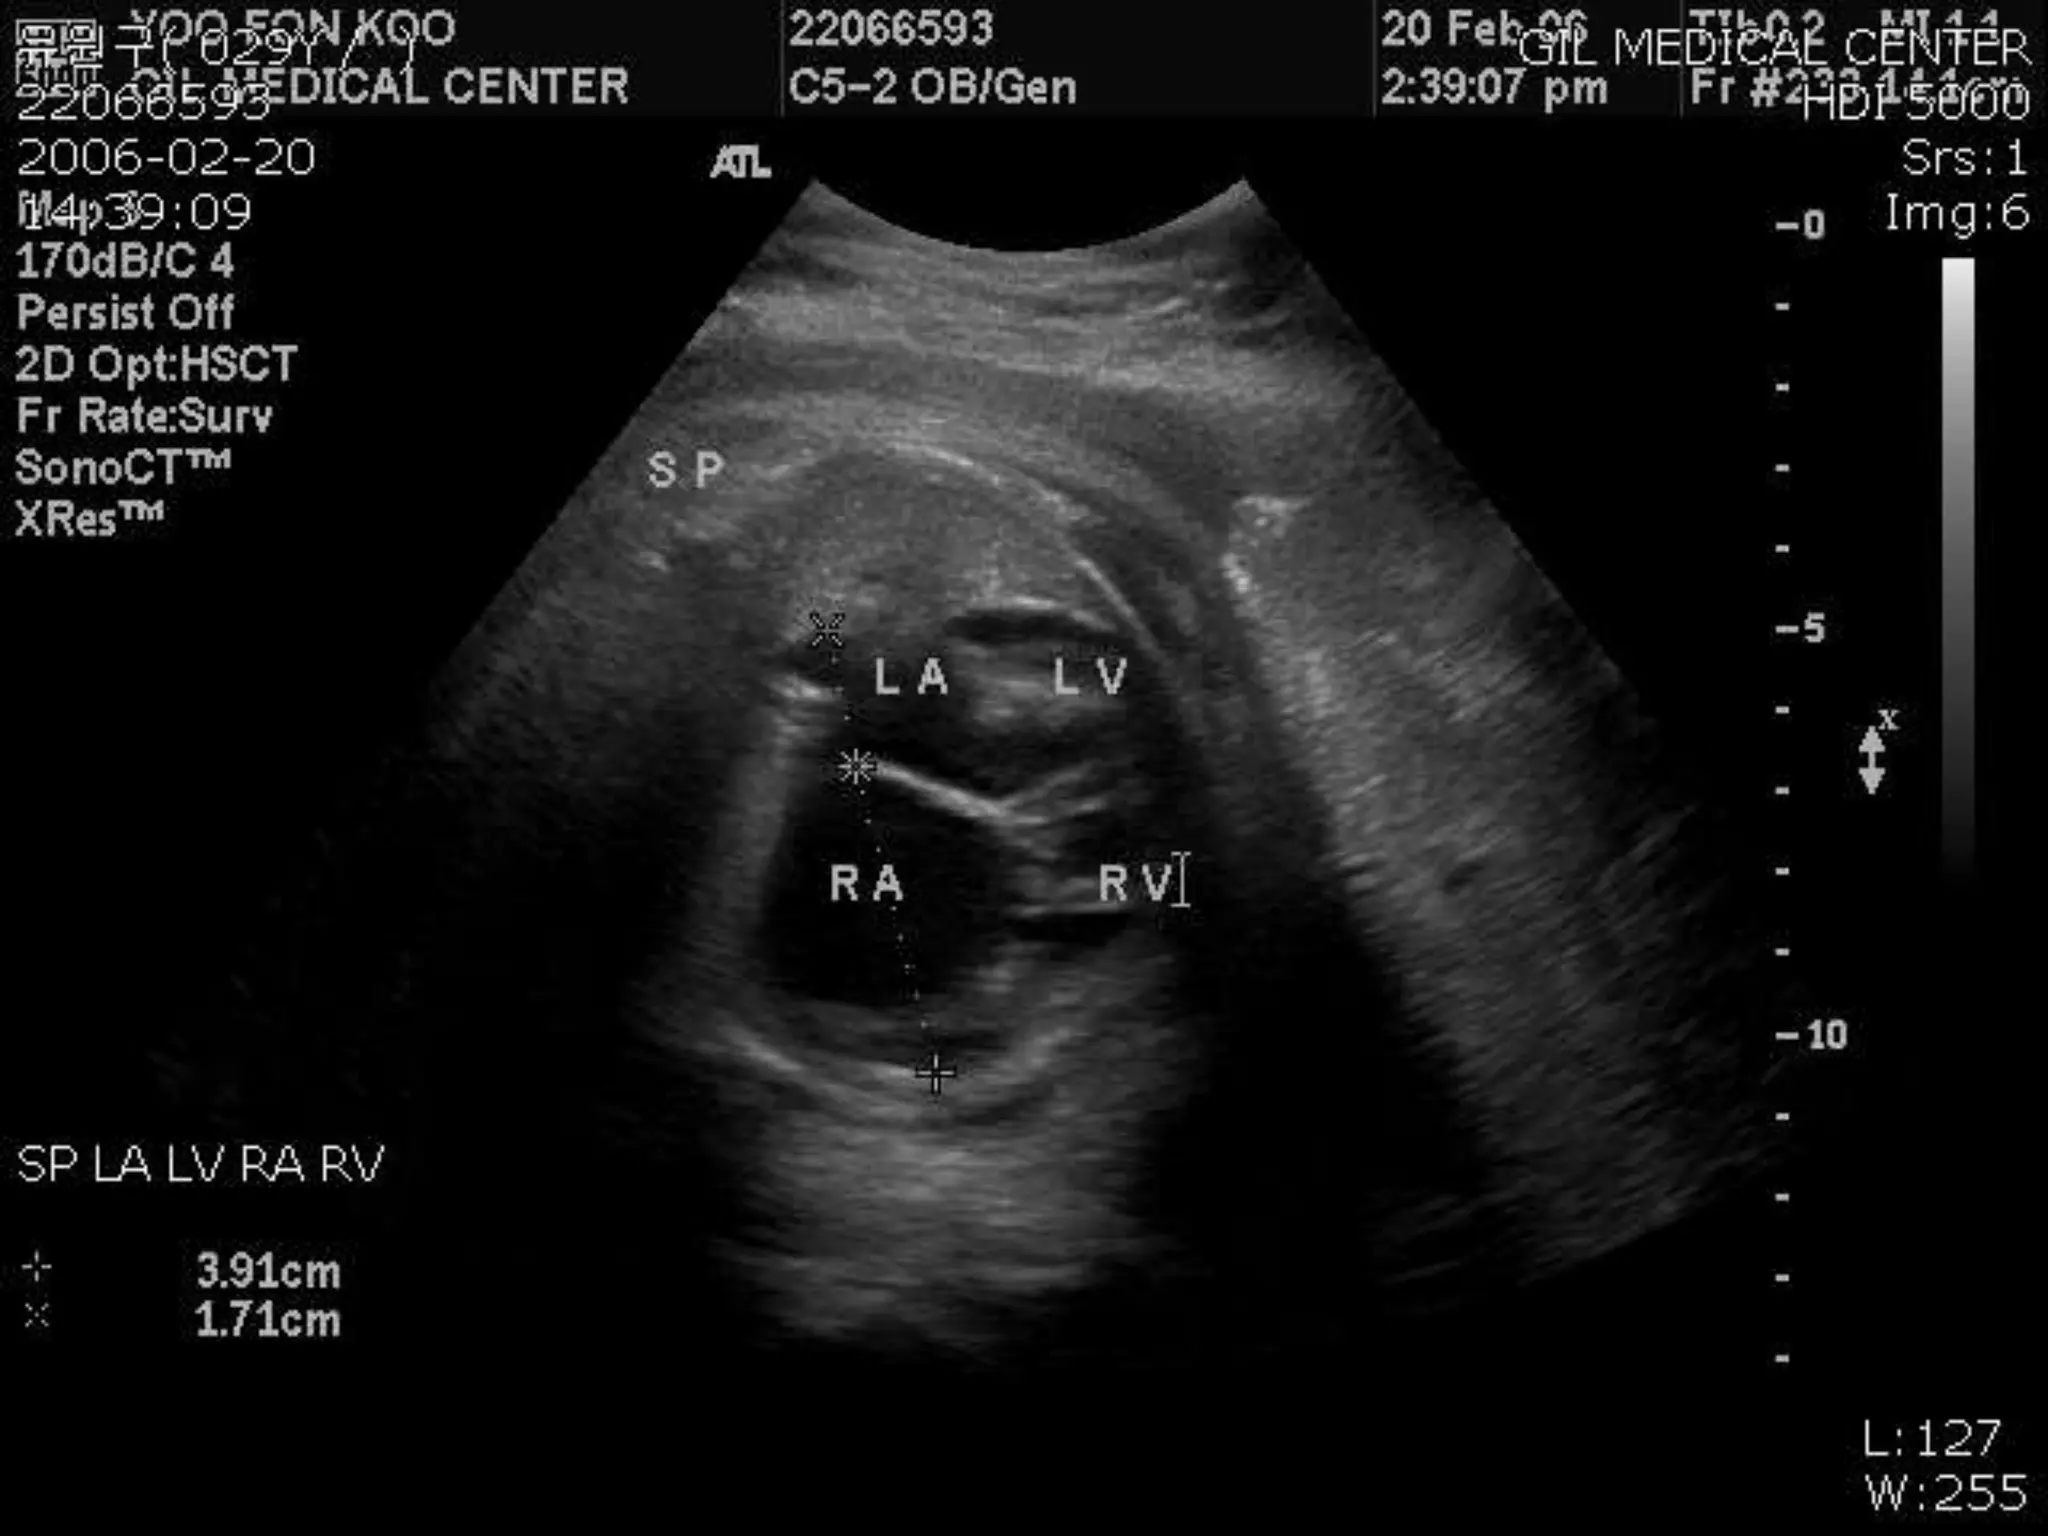

Severe Ebstein’s

malformation of tricuspid

valve (4-chamber view)

showing marked downward

displacement of shelf-like

posterior leaflet with

attachment to underlying

free wall by numerous

muscular stumps

(arrows), markedly dilated

atrialized portion of right

ventricle (ARV), small

functional portion of right

ventricle (RV), leftward

bowing of ventricular

septum, and marked

dilatation of right atrium

(RA). LA indicates left

atrium; LV, left ventricle

Epidemiology